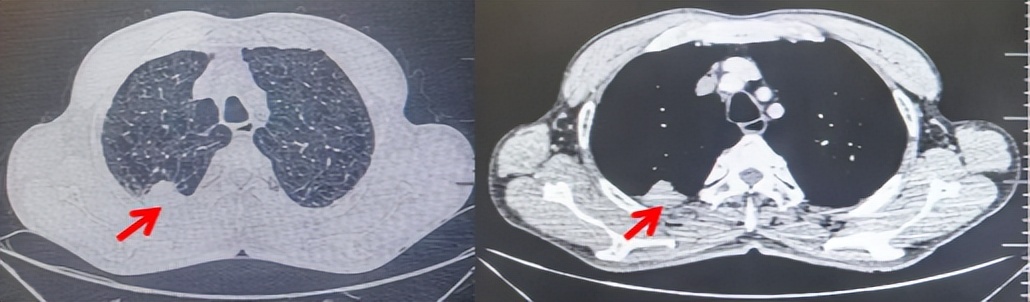

2024.09.12复查胸部CT示左侧胸膜结节,大者约为27mmx13mm,考虑转移可能性大,纵隔淋巴结增大,恶性?(如图6)。患者行胸膜穿刺活检取病理,结果示(胸膜)结合免疫组化,支持鳞状细胞癌,PD-L1(克隆号28-8)TPS约20%。分期为rT0N2bM1a IVA期,DFS为10个月。2024.09.24起行替雷利珠单抗联合紫杉醇+卡铂方案治疗4周期,复查胸CT评效SD(如图7)。后患者因脑梗塞停止治疗,于综合医院就诊,后未返院复查及治疗。

图6:患者胸膜及纵隔转移(2024.09)胸部CT肺窗及纵隔窗